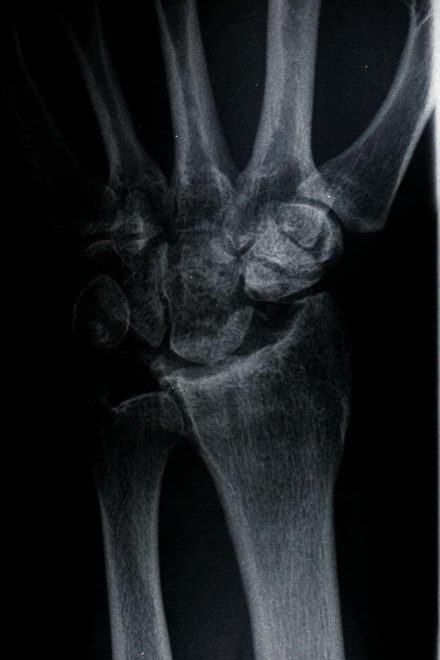

Skafolunat bağ yaralanmaları en sık görülen el bileği yaralanmalarıdır. Bu bağ skafoid ve lunat kemiği bir arada tutar. Bu bağın bozulması skafolunat instabilitesine neden olur. Geç aşamalarda skafoid ve lunat kemik arasında bir boşluk oluşur ve skafolunat ayrışması olarak bilinir.

Skafolunat ekleminin ayrıldığını gösteren bileğin stresli görünümü